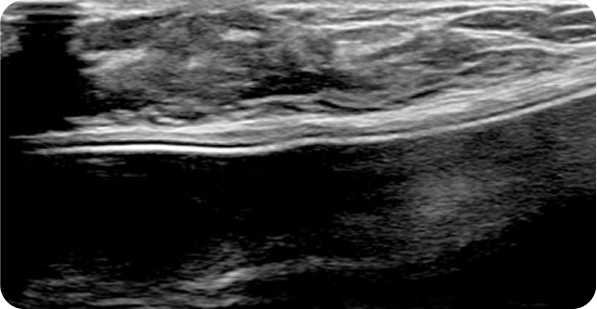

영상 특화 전문의니까

초음파 보면서

맘모톰도 안전하게